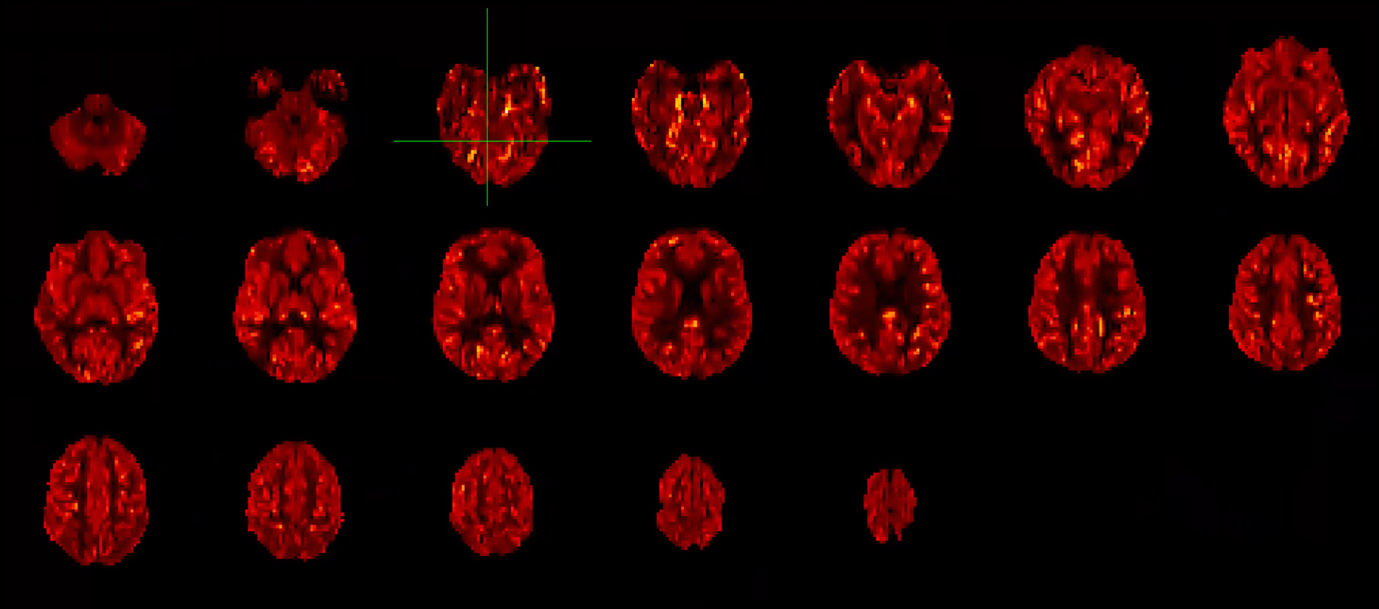

Caption: An image of blood perfusion in a healthy young adult acquired with UEA’s MRI scanner. Unlike conventional perfusion imaging, no radioactive tracers are required to produce these images, which show that the grey matter (e.g. the brighter “ribbon” around the edge of the brain) has higher perfusion that the white matter (located inside). This difference arises because the cells in grey matter have higher energy requirements than white matter, so need a greater supply of oxygen and glucose to function.

An exciting new study, being run by Professor Michael Hornberger, is using this arterial spin labelling pulse sequence to determine whether reductions in blood flow are related to cognitive decline, with particular focus on dementia.